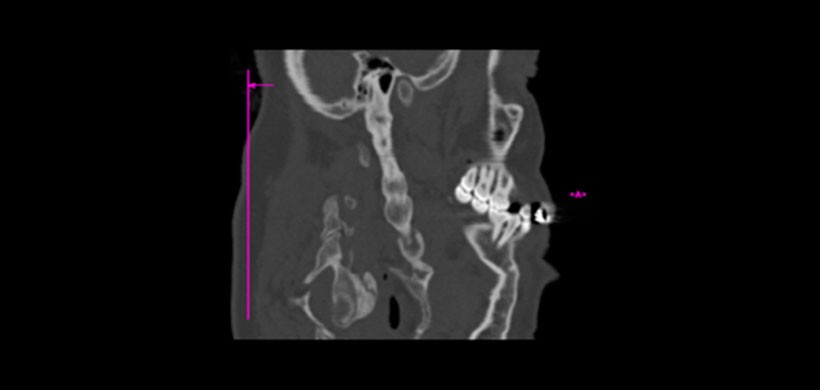

Se han utilizado múltiples modalidades de estudio imagenológico para confirmar el diagnóstico clínico, incluyendo las radiografías lateral de cuello y anteroposterior de cráneo, panorármica, la tomografia computarizada de haz cónico (TCHC) y la tomografía espiral multicorte (TEM) La técnica de elección para el diagnóstico y evaluación del síndrome de Eagle es el TEM con reconstrucción 3D. Permite obtener información del tamaño, dirección y relación del complejo estiloideo con las estructuras vasculonerviosas cercanas

Figura 2. Tomografía de haz cónico (TCHC), es unos de los examenes ideales para determinar la mineralización, el grosor y la angulación de los procesos estilohioideos. En la imagen se muestra una vista sagital donde se visualiza una mineralización con un importante espesor del proceso estilohioideo del lado derecho.